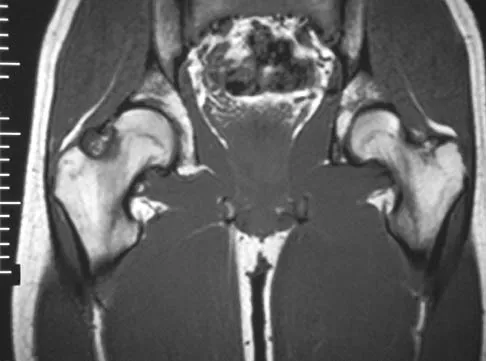

Figures 4a through 4c show the radiographs, CT scans, and T1-weighted MRI scan of a 19-year old man who has had increasing right hip pain and decreasing range of motion for the past several years. He also reports intermittent "locking" of the hip. What is the most likely diagnosis?